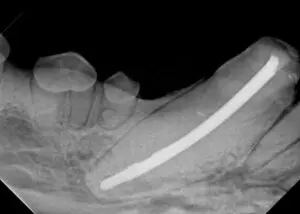

Root canal therapy of the right mandibular canine tooth

After a tooth receives root canal therapy, it is wise to radiograph that tooth at the 6-9 month date. This allows us to see if the surrounding bone at the apex of the tooth is healing and infection is resolving. After this procedure, we will recommend evaluating every 12 months, which can be done at the time of the annual dental evaluation and cleaning/probing/charting/dental x-rays/CBCT. As a matter of fact, any time a root canal therapy has been performed, this should be followed annually, so it may be best to have us perform the annual cleaning with the blessings of your family veterinarian.